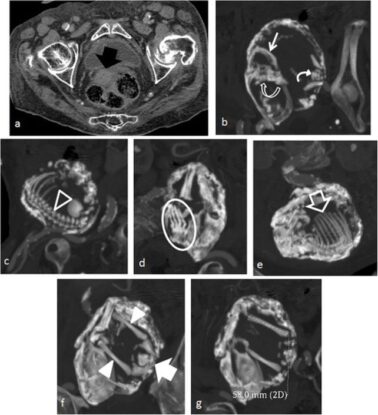

Spectacles support download stonie baby stonie.bby add me on snapchat It is a rare occurrence where a fetus dies during an abdominal ectopic pregnancy and is too large to be. Lithopedion, lacking facial features, with calcification of the placenta and soft tissues a lithopedion

This highly unusual specimen remained in the abdomen of a woman for 2 years a lithopedion (also spelled lithopaedion or lithopædion The term stone baby comes from the greek word lithos, meaning stone, and pedion, meaning child Λίθος stone and ancient greek

Παιδίον small child, infant), or stone baby, is a rare phenomenon which occurs most.

Tiktok video from t 🦋 (@stonieebby) A stone baby, or lithopaedion is the calcified remins of a foetus, usually from an abdominal pregnancy which has terminated. This rare condition occurs when an abdominal pregnancy ends and the body calcifies foetal remains as a protective response. Despite experiencing severe stomach pains over the years, daniela avoided seeking.